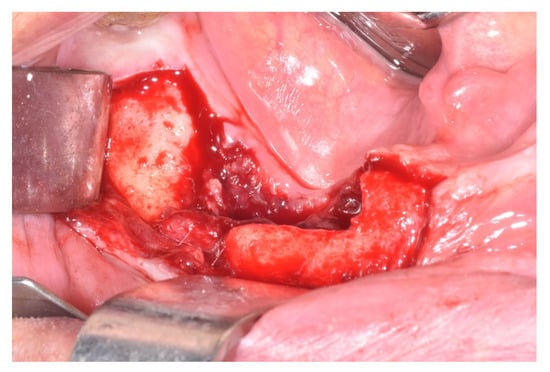

| Treatment | ||||||||

| Surgical | x | x | x | 3 | 10 | |||

| Submarginal resection | x | x | 2 | 3 | ||||